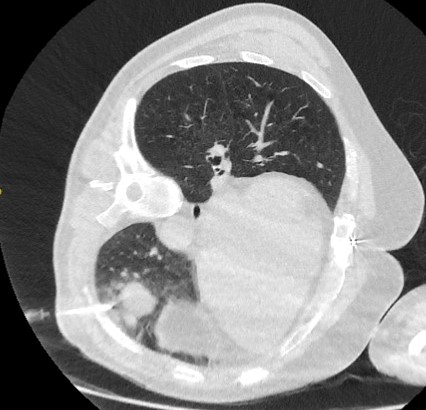

Nódulos com opacidade em vidro fosco: um crescimento de 2 mm no diâmetro máximo deve ser considerado potencialmente significativo, enquanto o desenvolvimento de um componente sólido sugere a necessidade de considerar uma investigação e/ou tratamento adicionais.[Figure caption and citation for the preceding image starts]: Tomografia computadorizada (TC) mostrando nódulo com opacidade em vidro fosco no lobo superior esquerdo. Este foi eventualmente ressecado após 2 anos de vigilância em decorrência de crescimento, e a histopatologia confirmou adenocarcinoma de pulmão com padrão mucinoso-lepídico mistoDo acervo de Dr. George Tsaknis, MD, PhD, FRCP (Londres), MRQA, MAcadMEd, PGCert; usado com permissão [Citation ends].